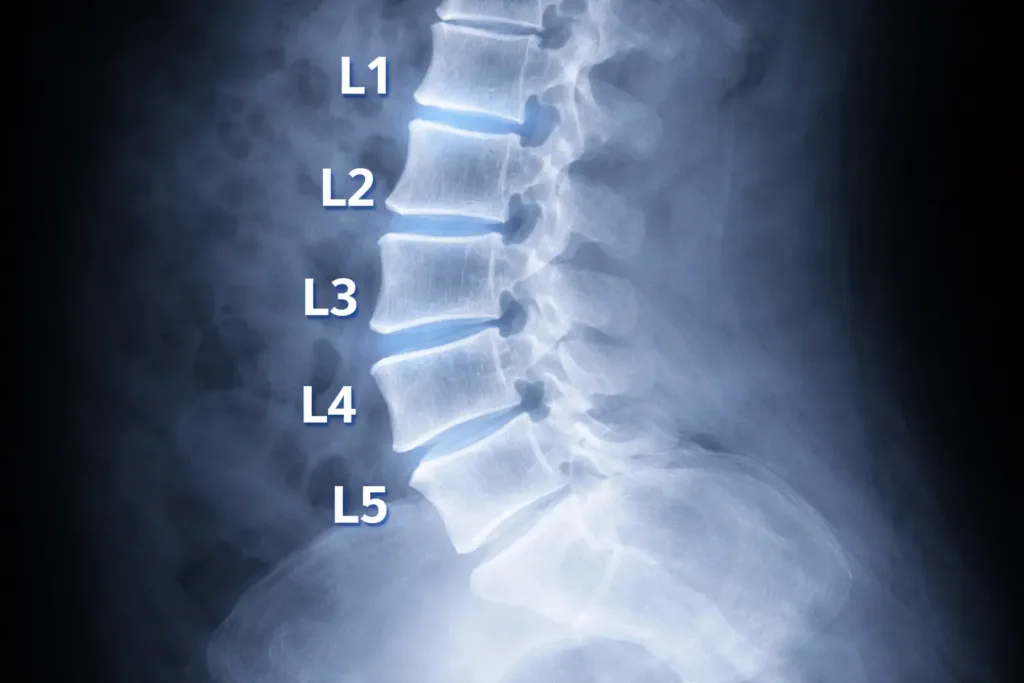

The lumbar spine: usually five vertebrae

The lumbar spine typically has five vertebrae: L1, L2, L3, L4, and L5. They sit between the rib-bearing thoracic spine (T12 is just above L1) and the sacrum (S1 is just below L5).

On imaging, L5–S1 is the most discussed level because it is the junction between the mobile lumbar spine and the fixed pelvis.